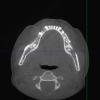

SergeyAL Опубликовано 27 мая, 2013 Поделиться Опубликовано 27 мая, 2013 у пациентки трехмерный костный дефект далее проведена трехмерная костная пластика, доступ латеральный тоннель рана ушита послойно получен хороший объем костной ткани получена костная ткань хорошего качества, хорошо кровоснабжаемая 5 Ссылка на комментарий